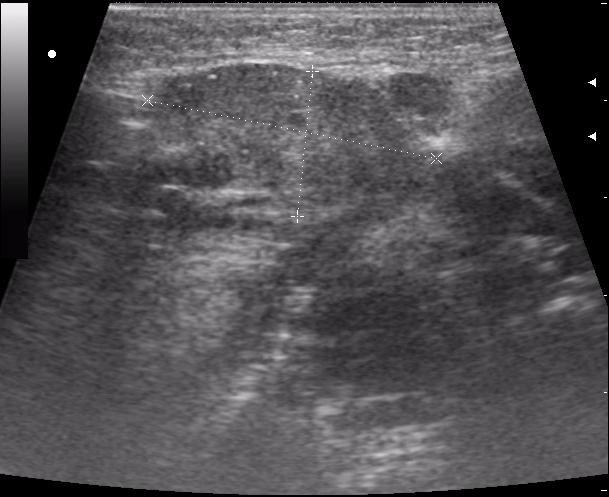

пакеты гиперплазированных лимфоузлов